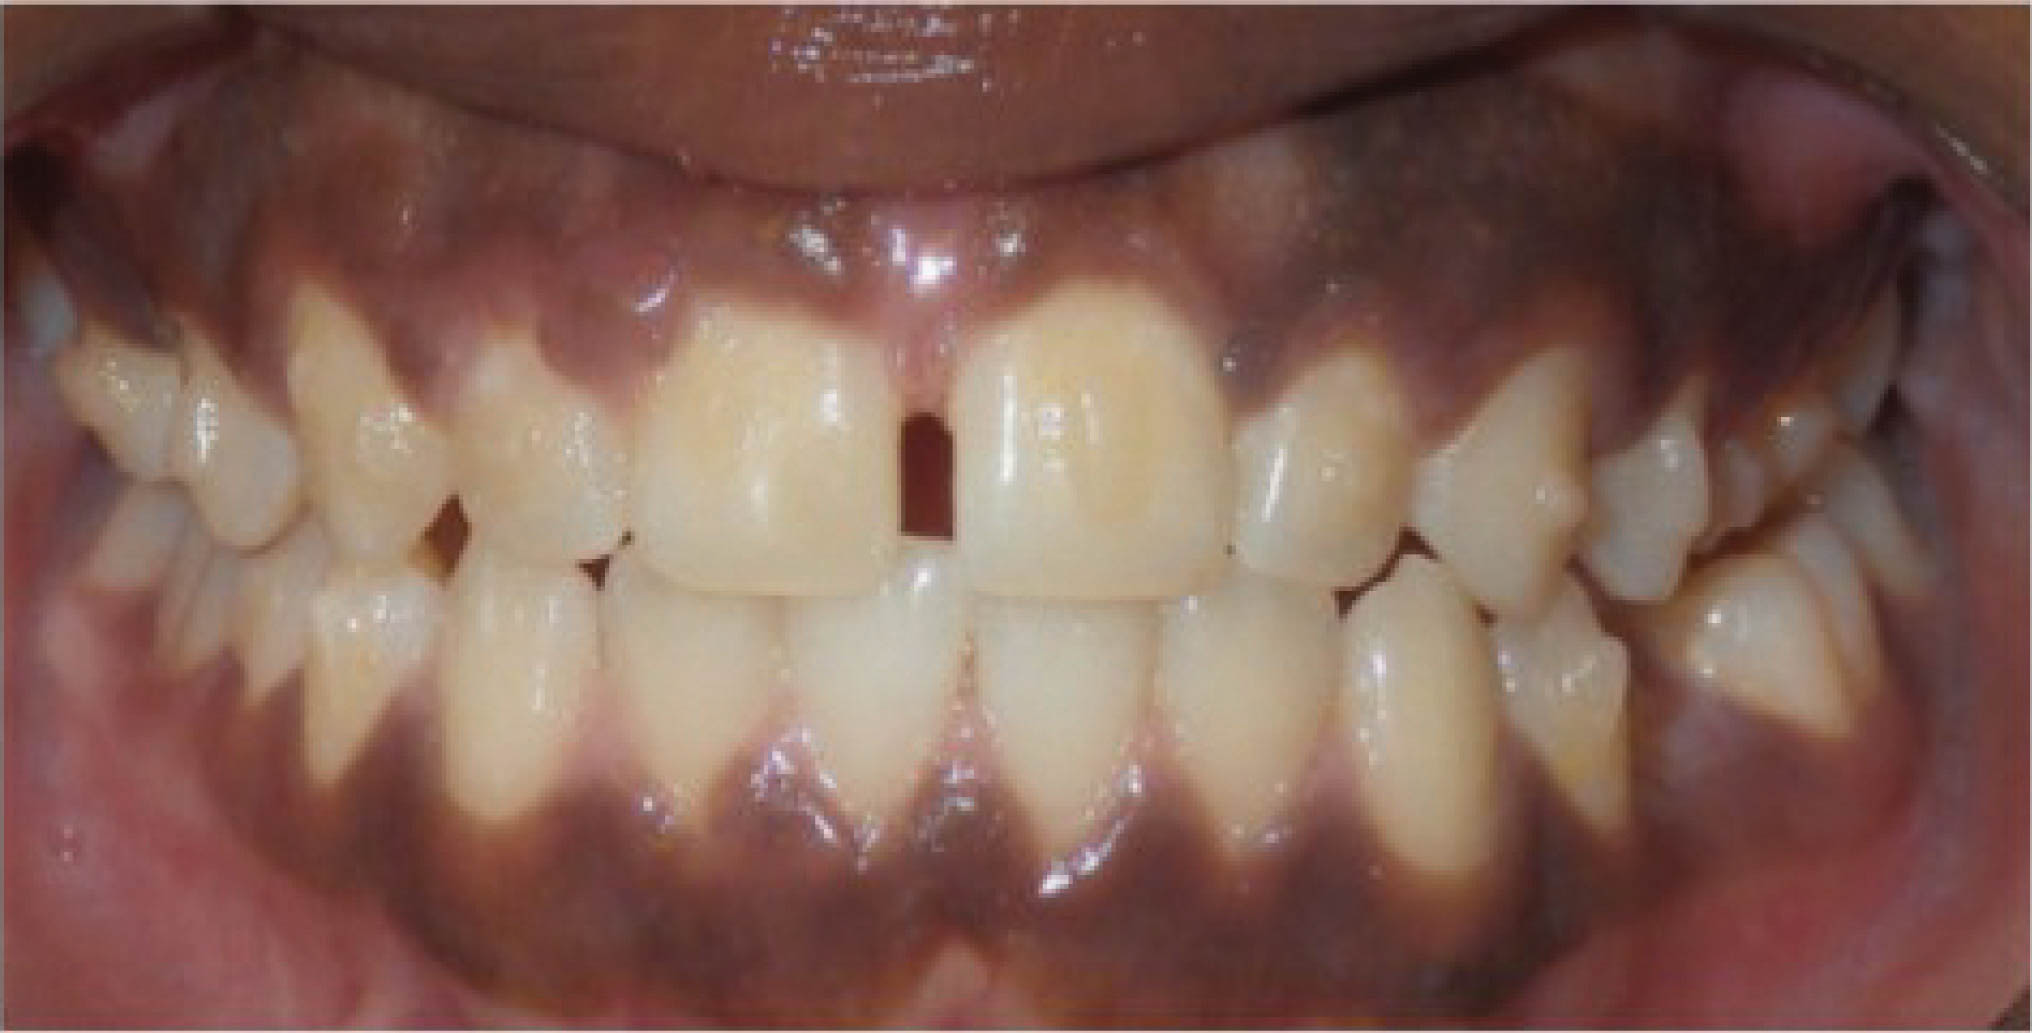

در بیماری که در شکل 38-6 مشاهده میکنید، یعنی بیماری که سانترالهای بالا او از هم به صورت تیپینگ دور شدهاند، درمان با الاینر خیلی عالی میشود، و تصویر آخر نرم افزار به نتیجه درمان خیلی شبیه میشود (شکل 39-6 و 40-6).

شکل 39-6

شکل 40-6